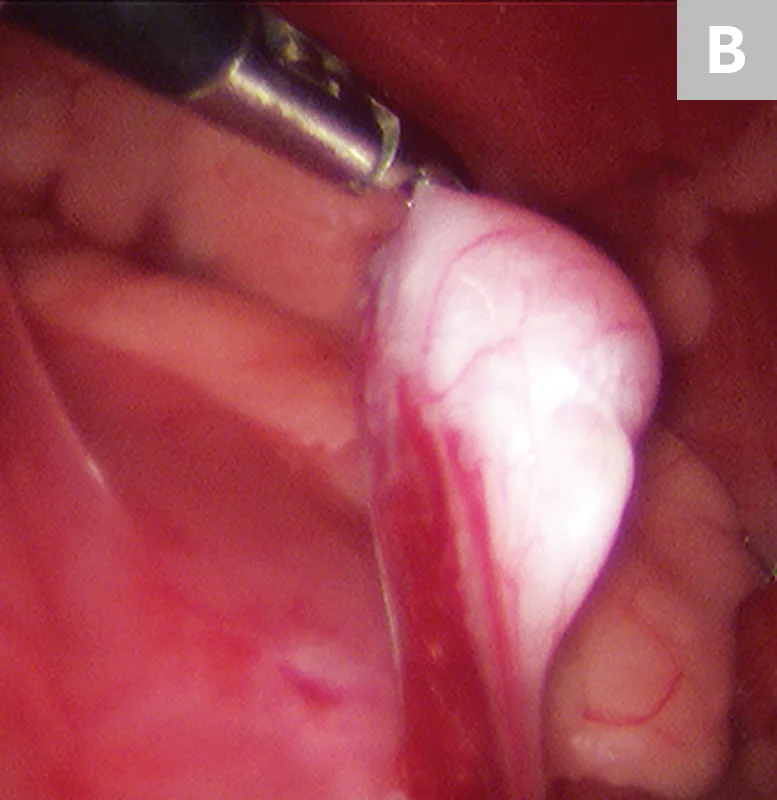

FIGURE 4

Laparoscopic liver biopsy using a 5-mm cup biopsy instrument. A minor degree of hemorrhage from the previous biopsy site can be seen.

After placement of 2 ports and insufflation of the abdomen, the liver is examined and the lesion or lobe(s) to be sampled are identified. The lesion is grasped, then held in place for 15 seconds before the biopsy sample is removed (Figure 4). The biopsy site should be monitored for excessive bleeding. After adequate hemostasis is ensured, the port incisions are closed routinely. The lateral recumbency position prevents complete visualization of the dependent lobes; however, it does not preclude performing biopsies, if necessary.